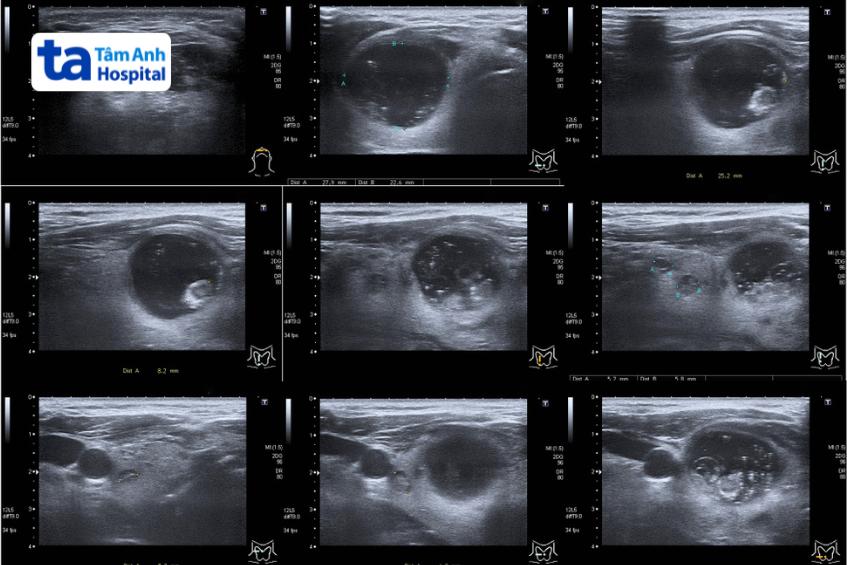

Hình ảnh nhân giáp được phân loại Tirads 3.